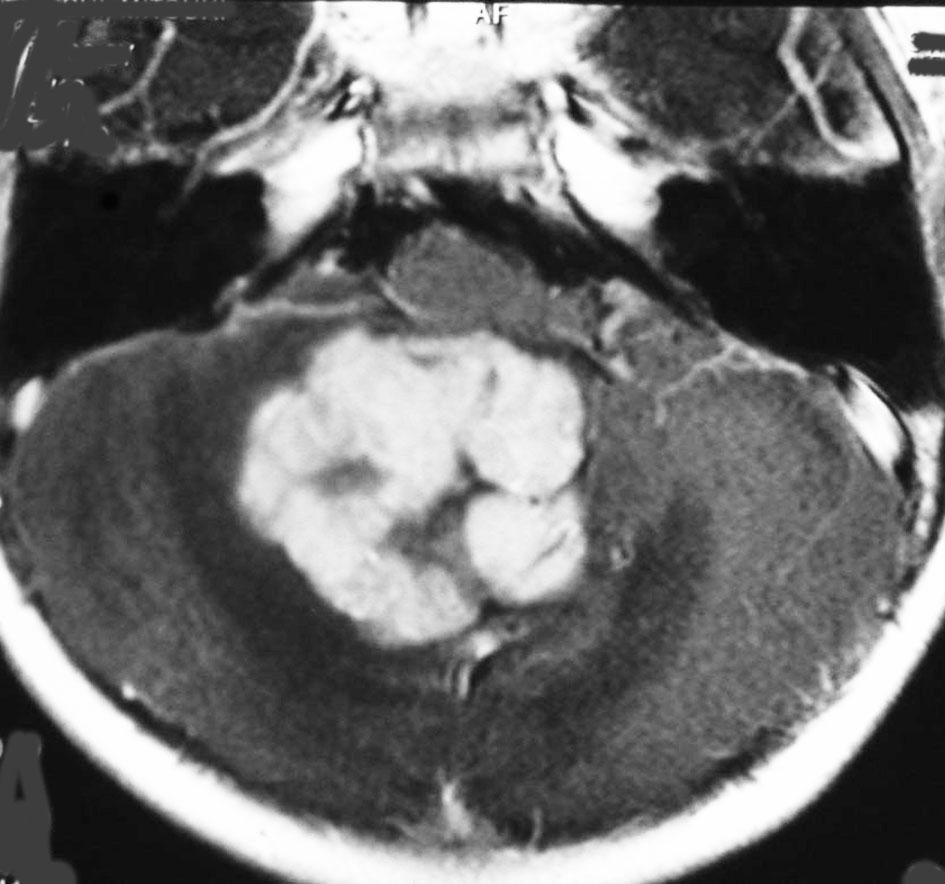

- MRIで診断します

- 境界がはっきりした腫瘍です,くりんとしています

- ガドリニウム造影剤で白く映ります(増強される)

- でも,ガドリニウム造影剤が入らなくて白く映らないものもあります

- 周囲の小脳が腫れることが多いです(脳浮腫)

典型的な小脳虫部(小脳の真ん中)の髄芽腫です。横の方,ルシュカ孔へ伸びていないので上衣腫と区別できます。ガドリニウムという造影剤で白く写っています。